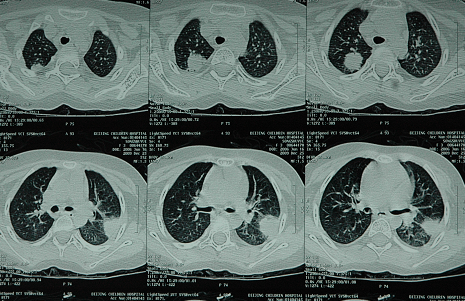

既往诊治经过:11月龄时再次因“发热、感染”住院,血常规示三系减少,辅助检查:头颅MRI平扫提示:右侧颞叶、顶叶、右侧内囊后肢、外囊异常信号影,考虑为脑炎可能性大;1岁龄突发癫痫抢救--头部CT:右侧顶叶皮层下脑脓肿;2-4岁期间疾病进入相对稳定期,三系仍低,但无需输血支持,偶有发热,感染相对较容易控制,但生长发育及智力较同龄儿童明显落后; 4岁时再次因“发热、癫痫发作”住院,血常规:WBC:2.5×109/L,N:0.8×109/L,HGB 54g/L,PLT 32×109/L,骨髓形态:增生重度减低,红系极少,未见巨核,骨髓活检:粒红比例略增大,幼稚阶段细胞略多见,红系各阶段细胞可见,巨核细胞少见,网状纤维染色(-) 胰腺CT:胰腺密度普遍性减低,为脂肪密度影,诊断:胰腺萎缩。入院前反复感染。

入院后诊治经过:+15 天粒细胞植入;+59 天血小板植入;+30,60,90天连续监测患者嵌合率都为100%供者型,骨髓微小残留未见异常。并发症:真菌肺炎-伏立康唑,CMV血症:丙球+更昔洛韦。移植后三年,血液学持续完全缓解,血常规正常,停用免疫抑制剂,无GVHD表现,目前消化科、生长发育科(内分泌科)随诊中。